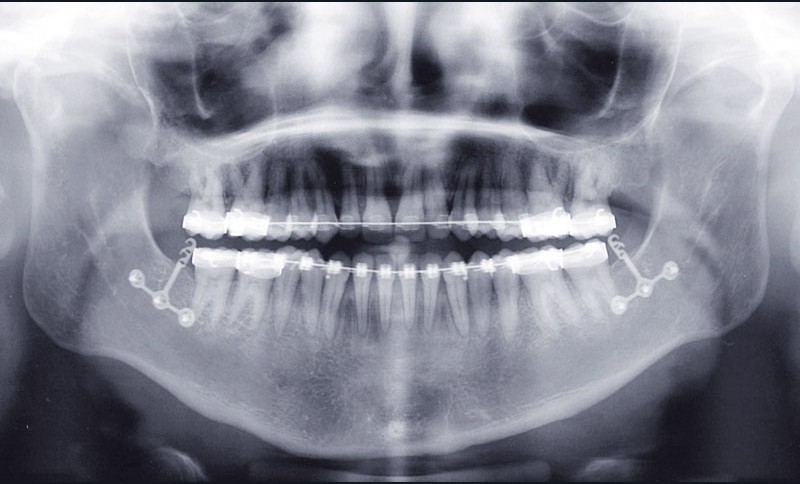

Étapes de traitement

(fig. 2, 3, 4, 5 et 6)

Le plan de traitement retenu a été le suivant :

– disjonction maxillaire assistée chirurgicalement

– préparation orthodontique avec recul molaire mandibulaire sur miniplaques à l’aide de corticotomies alvéolaires

– chirurgie d’avancée mandibulaire et génioplastie soustractive verticale

Distalisation molaire mandibulaire par corticotomies associées aux miniplaques (fig. 7)

Avantages

Le recul molaire a apporté l’espace nécessaire à la correction de l’encombrement avec en plus un léger recul incisif qui a permis de positionner de façon idéale l’incisive dans la symphyse. Une distalisation des secteurs latéraux de 3 mm à droite et 2 mm à gauche permettant aussi de symétriser les relations molaires a donc été obtenue en…